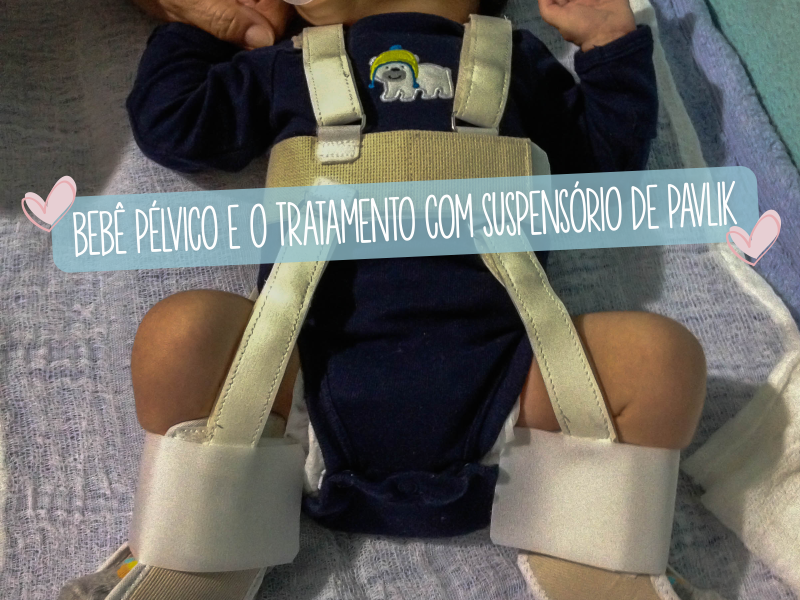

O que o bebê pélvico tem de diferente e por que isso acende um alerta para a saúde do quadril?

Mas o que isso realmente significa para a saúde do seu pequeno? A verdade é que essa posição pode aumentar um pouquinho o risco de algo chamado displasia do quadril (DDQ).

Pode parecer assustador, mas vamos combinar que é mais um ponto de atenção. Essa condição se caracteriza por uma instabilidade na articulação do quadril, e os bebês que ficam nessa posição precisam de uma avaliação mais cuidadosa pelos ortopedistas pediátricos.

O ultrassom dos quadris logo após o nascimento se torna um exame chave nesses casos. Ele ajuda a gente a identificar precocemente qualquer sinal de que algo não está 100% no lugar, garantindo que o desenvolvimento do seu bebê seja saudável desde o início.

Agora, vamos ao ponto que mais te intriga: um bebê pélvico tem algum problema? A gente precisa ser bem transparente aqui. Sim, existem alguns riscos que são mais frequentes nessa posição, e o principal deles é a Displasia do Quadril (DDQ). Isso porque a posição sentada dentro do útero pode forçar a articulação do quadril do bebê, tornando-a mais instável.

“É essencial que todo bebê que permaneceu em apresentação pélvica seja avaliado por um ortopedista pediátrico e, na maioria dos casos, faça um ultrassom dos quadris após o nascimento. Essa é uma medida de prevenção crucial para identificar e tratar precocemente qualquer instabilidade.”

Aqui está o detalhe: após o nascimento de um bebê que esteve pélvico, os cuidados não terminam. Como mencionamos, o risco de Displasia do Quadril é maior. Por isso, a avaliação ortopédica pediátrica e o ultrassom dos quadris são fundamentais para um diagnóstico precoce e, se necessário, o tratamento adequado. Fique tranquila, a maioria dos casos de DDQ é tratada com sucesso quando identificada cedo.